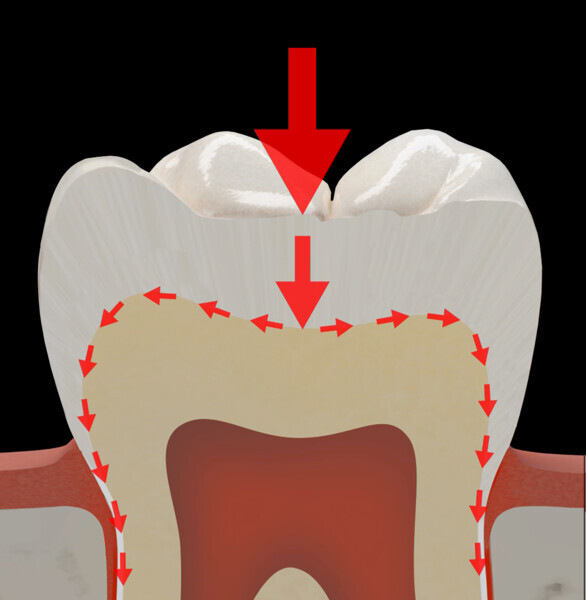

In the MiCD restorative domain, direct composite resin plays a key role owing to its fundamental advantages. These include being aesthetic, biocompatible and mercury-free, having low thermal conductivity, allowing minimally invasive restoration and supporting the dental tissue remaining after caries removal. However, long-term clinical efficacy, especially in the case of large restorations, endodontically treated teeth, cuspal restorations and large Class V restorations, is limited by the susceptibility to crack formation and propagation. The longevity of composite resin restorations is inversely proportional to their size. Larger restorations are more prone to failure, often due to fractures, especially in teeth with significant crown destruction.1

Based on the interpretation of clinical studies, fracture is the most common reason for failure of a composite restoration, followed by secondary caries and loss of retention.2–6 According to long-term studies, the failure rate of Class II cavities after ten years ranges between 15% and 20% and is mostly associated with fractures.

The limitations of direct composite resin include low fracture toughness and issues related to polymerisation shrinkage. To address these challenges, recent advancements in dental materials have highlighted the significant benefits of incorporating fibres into both direct and indirect composite resin restorative materials.

In addition to their reinforcing capabilities, fibres enhance the resistance of restorative materials to mechanical forces by acting as stress breakers and dispersants, and they reduce polymerisation shrinkage. In recent years, composite resin materials into which fibre has been integrated, popularly known as fibre-reinforced composites (FRCs), have become increasingly popular in dentistry.

The first step in the MiCD Fiber Filling 4R protocol involves recognising the tooth status, existing occlusal forces and potential tooth preparation design. This starts with a thorough assessment of the patient’s dental condition, occlusal patterns and occlusal contact mapping using articulating paper of suitable thickness and the progressive colour transfer technique. Every tooth has its own stress pattern, and each contact location on a tooth behaves differently under stress. Recognising these patterns is vital for designing a restoration that avoids potential failure in the long term. Additionally, designing the restoration with tooth and restoration reinforcement in mind helps address specific structural requirements and challenges, ensuring that the final outcome is both functional and durable.